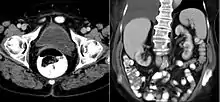

القيلة الحالبية[1] (بالإنجليزية: Ureterocele) هي عبارة عن خلل خِلقي يحدث في الحالب، حيث ينتفخ الجزء البعيد من الحالب عند موضع فتحته في المثانة، فيما يشبه الكيس. وغالبا ما ترتبط هذه الحالة مع تضاعف نظام الجمع، الذي يكون فيه حالبان مسئولان عن صرف الكلية الخاصة بهما بدلا من حالب واحد. تمثل القيلة الحالبية البسيطة، التي تنطوي على حالب واحد فقط، 20% من الحالات. ويؤثر هذا المرض على واحد من كل 4000 شخص، على الأقل أربعة أخماسهم من الإناث. وفي كثير من الأحيان يكون المرضى من العرق القوقازي.

منذ ظهور الموجات فوق الصوتية، يتم تشخيص معظم حالات القيلة الحالبية قبل الولادة. وغالبا ما يتم العثور على حالات الأطفال والكبار بالصدفة، من خلال التصوير التشخيصي الذي يتم إجرائه لأسباب غير ذات صلة.